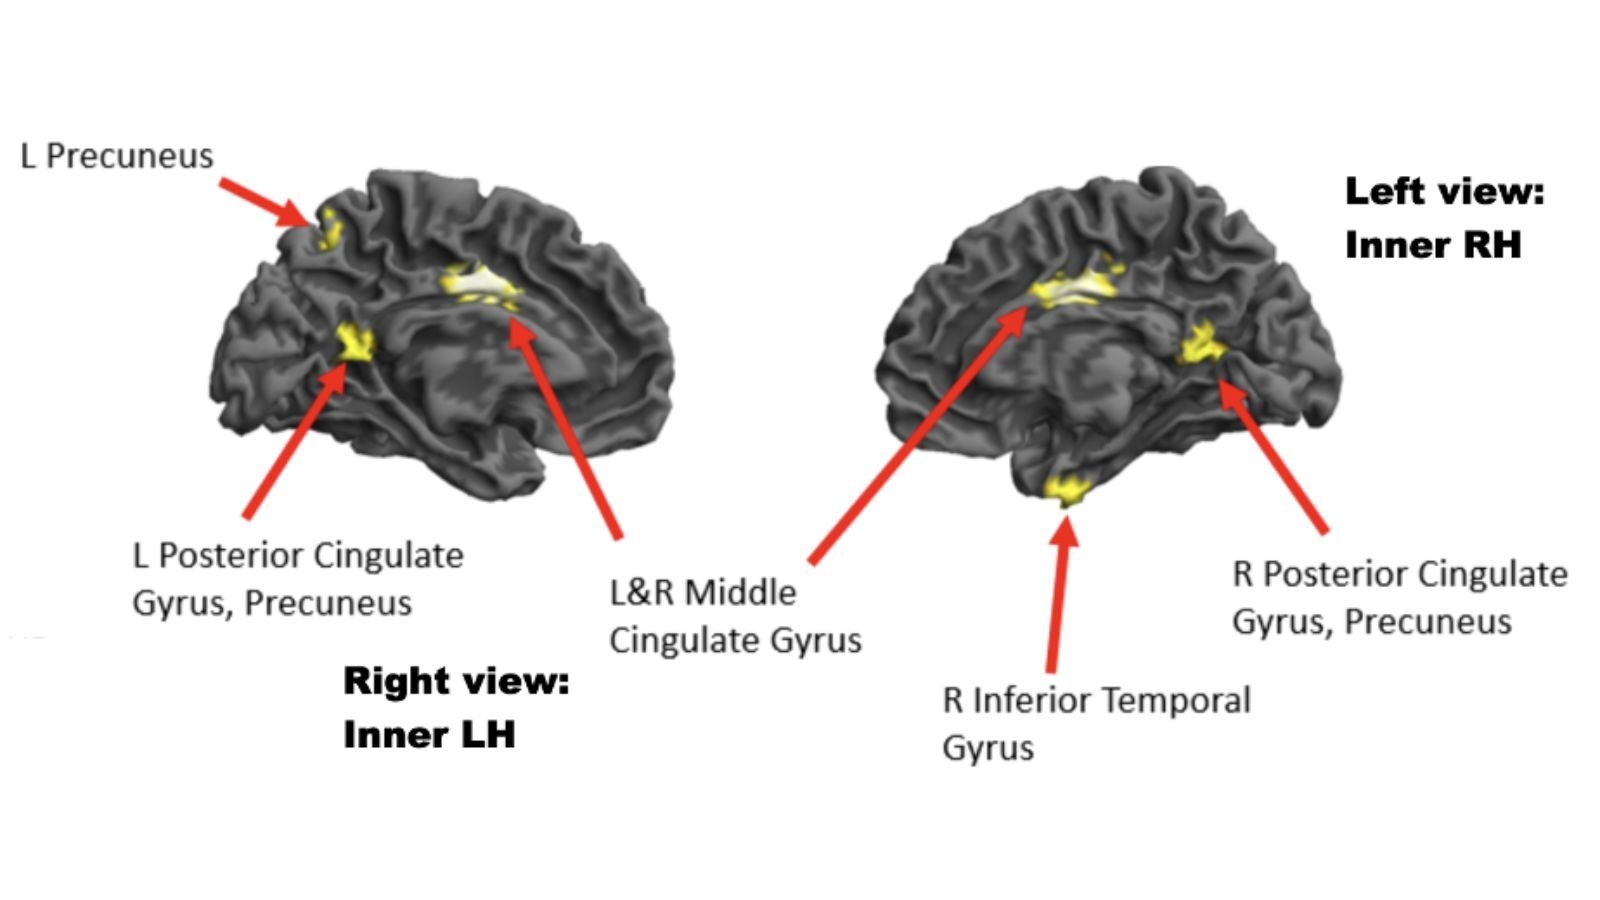

Flow State Uncovered We Finally Know What Happens In The Brain When You re in The Zone Live Science